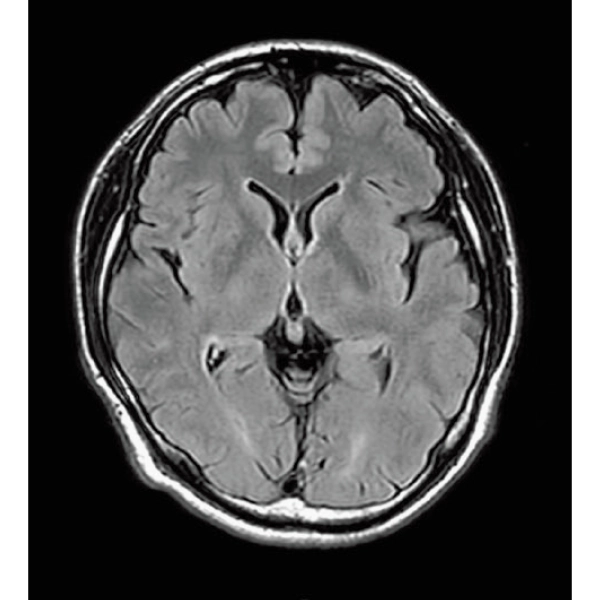

ShortScan

FLAIR, 1:14

DWI, 0:36